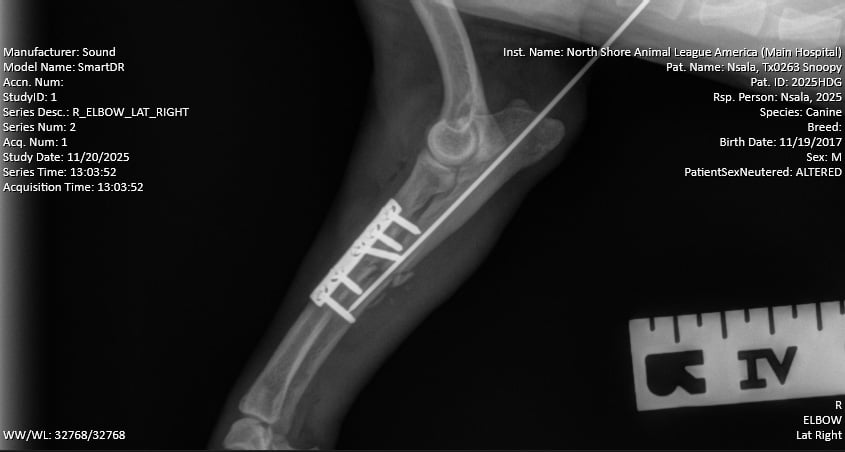

Snoopy, a two-year-old hound mix, arrived wearing a splint. X-rays revealed, however, that the splint was doing more harm than good. “His radius and ulna were completely fractured, and the bones inside the splint had shifted,” said Dr. Verdino. “If left to heal that way, the leg would have ended up several centimeters shorter and completely nonfunctional. Ultimately, it would have been amputated.” Instead, Snoopy underwent surgery to stabilize the limb. “We placed a metal plate and screws on the radius and a small pin on the ulna. Surgery went well, and he’s already weight-bearing. His long-term outlook is excellent.”